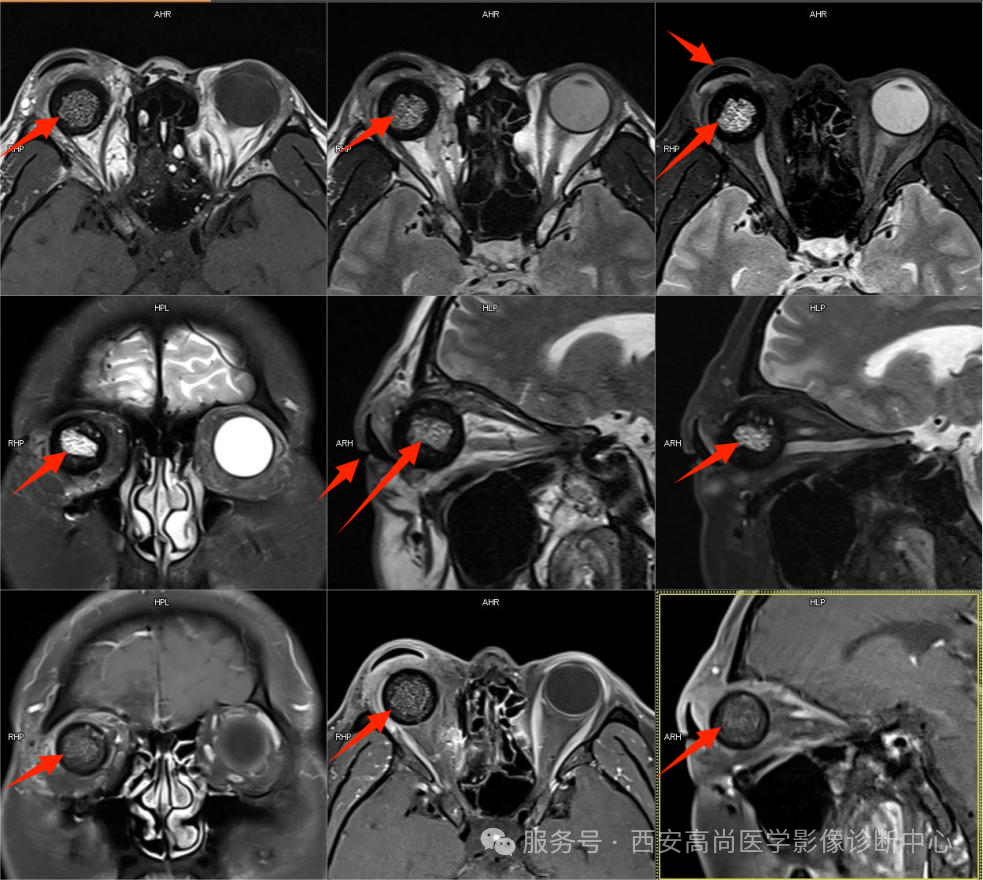

淋巴瘤

右侧眼眶内见一不规则结节样 T1 等信号,T2-FS 稍高信号,跨肌锥生长,与右侧视神经边界欠清晰,增强呈中等以上均匀强化,强化程度低于眼肌,强化边界清晰。